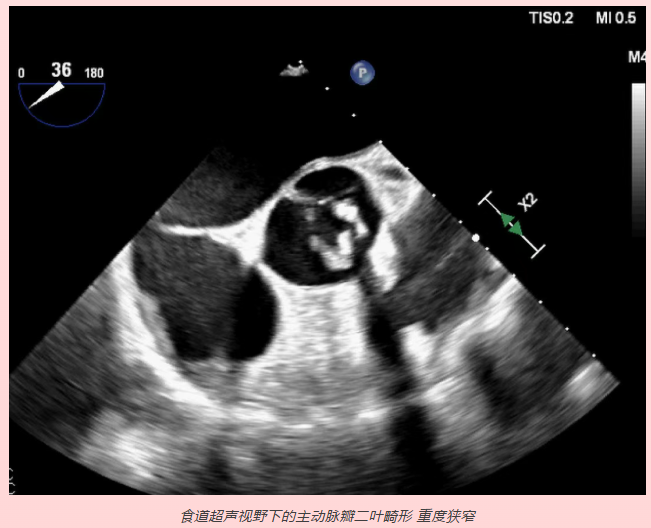

4.心脏瓣膜病、感染性心内膜炎、心脏占位性病变及心脏介入手术等,如瓣膜狭窄、关闭不全、脱垂及腱索断裂、心尖血栓、心房粘液瘤等。